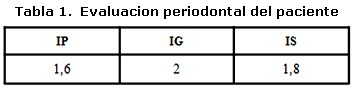

Un varón de tres años de edad con diagnostico de Histiocitosis de Células de Langerhans con afección ósea multifocal y otros sitios especiales fue referido al Servicio de Odontopediatría del Hospital Universitario de Maracaibo por el Servicio de Oncología Pediátrica del mismo Hospital, para valoración. El examen médico reveló, exoftalmos, palidez mucocutánea con pápulas eritematosas, lesiones hipercrómicas en miembros inferiores, dermatitis seborreica en cuero cabelludo, múltiples adenopatías cervicales y otitis supurativa recurrente. El informe de las pruebas de laboratorio indicó anemia y diabetes insípida. La biopsia de cuero cabelludo y el estudio inmunohistoquímico de la muestra tomada (Figura 1, 2 y 3) confirmaron el diagnóstico clínico, mientras que el examen de líquido cefalorraquídeo y médula ósea reportaron ausencia de infiltración. En las imágenes de resonancia magnética cráneo-facial, se evidenció realce anormal sugestivo de infiltración de huesos de base craneana y fosa anterior y media, mientras que la tomografía axial computarizada, reportó ausencia parcial de arco cigomático del lado derecho e imágenes osteolíticas en hueso temporal y pared orbitaria externa del mismo lado, acompañadas de lesiones similares en techo de orbita del lado izquierdo (Figura 4). Otros estudios, como tomografía de abdomen, pelvis y tórax, electroencefalograma, Rx de huesos largos, tórax óseo y columna, no revelaron hallazgos de interés. Durante la evaluación odontológica, la exploración extraoral evidenció exoftalmos y las lesiones de piel antes descritas; intraoralmente se registró la presencia de placa dental, gingivitis y hemorragia (Tabla 1), acompañada de movilidad dental, bolsas periodontales y recesión gingival (Figura 5) en la zona posterior izquierda de ambos maxilares (Tabla 2), además de caries dental y erupción prematura del 26. Radiograficamente se observaron lesiones osteolíticas, de bordes mal definidos, que medían aproximadamente entre 0,5 y 1,5 cm. de diámetro, localizadas en relación al 64, 65, 26, 74, 75, 85, también se observó agenesia de los gérmenes del 35 y 45 (Figura 6). Para el momento de la evaluación odontológica el paciente estaba recibiendo tratamiento con vasopresina y quimioterapia con vinblastina y prednisona. El manejo odontológico incluyo una fase inicial preventiva en la cual se instruyo a los representantes y al niño sobre hábitos de alimentación, higiene bucal y técnicas de cepillado y una fase quirúrgica llevada a cabo bajo anestesia general. Previa valoración sistémica y premedicación con antibioticoterapia se realizaron exodoncias del 65, 26, 74, 75 y curetaje de las lesiones. El resultado de la biopsia del tejido encontrado en los maxilares reportó un infiltrado inflamatorio severo, constituido por acumulo de linfocitos, histiocitos espumosos y células plasmáticas, mientras que el estudio inmunohistoquímico realizado con proteína S-100 y CD1a resultó negativo. Después de dos meses de seguimiento, el paciente cicatrizó favorablemente con persistencia en el 64 de recesión gingival, exposición de dos tercios de la raíz distal y movilidad leve. Radiograficamente se observan signos de osificación en las zonas intervenidas, sin embargo, es necesario seguir monitoreando al paciente para descartar la aparición de nuevas lesiones (Figura 7).